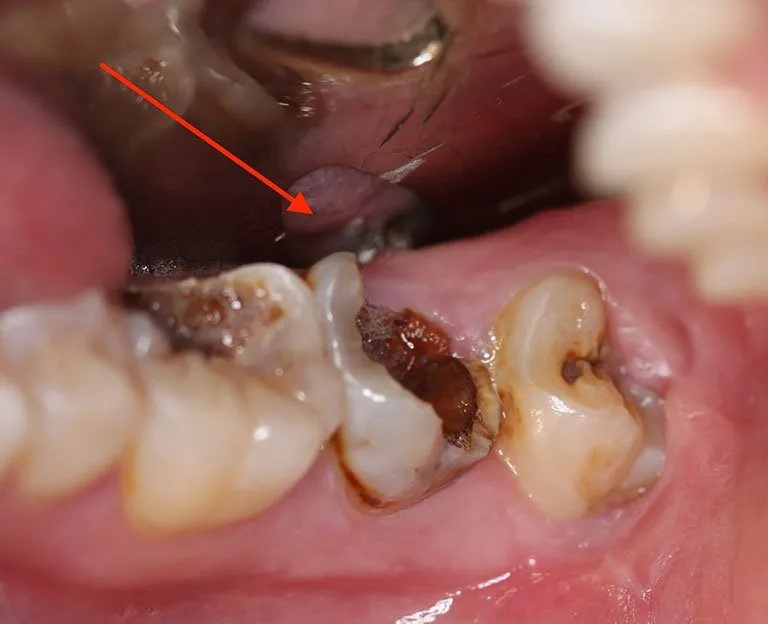

Răng Sâu Nặng là Gì? Định nghĩa răng sâu nặng: Răng sâu nặng là tình trạng sâu răng phát triển vượt mức, ăn sâu vào men răng,